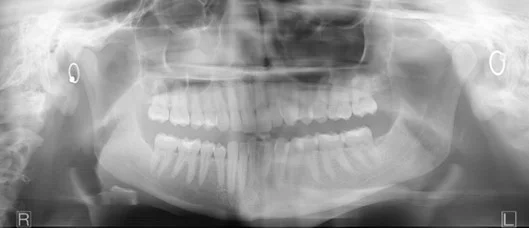

Dark area occluding maxillary apices

This is probably one of the most common problems we see with busy offices taking panoramic images. However, this symptom can be tricky to get rid of.

The most common root cause of this artifact is the patient failing to hold their tongue flat against the top of the hard palate. While most operators are aware of this recommended step, there are two additional lesser-known facts that may thwart dental professionals trying to remove this artifact from their images.

First, simply telling the patient to “put your tongue to the top of your mouth” may not solve this problem. The reason for this is that many patients may take this direction to mean they should simply touch the roof of their mouth with the tip of their tongue. This approach will not solve this problem because the goal is to remove the air gap between the tongue and the hard palate. Instead, we recommend that the operator should instruct the patient to “press the tongue flat against the roof”, which will better remove the air gap that can cause this artifact.

Another challenge for the office is that there is a very similar-looking artifact that may present for a completely different reason. If a large cross sectional area of the hard palate is between the x-ray source and the mandibular apices, this can absorb x-rays exposing this region, and can result in the dark artifact. This can be caused if the occlusion of the patient is “too flat”. The ideal approach to avoid this is to position the patient with a slight (~10 degree) downward tilt of the occlusal plane.